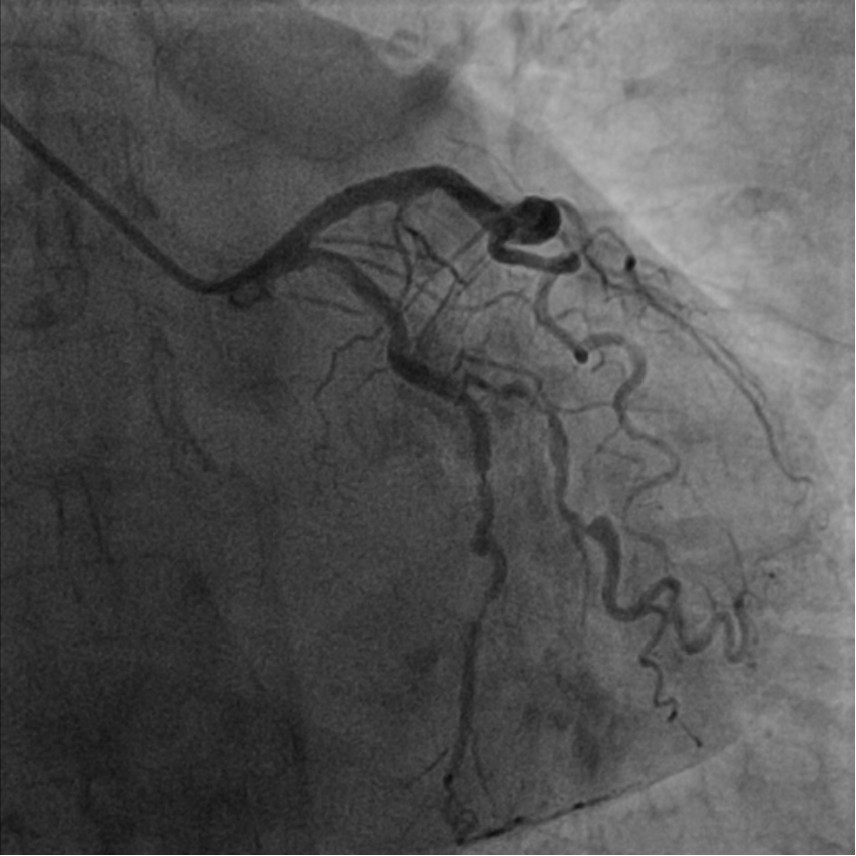

冠脉造影

冠脉三支病变 右冠优势型,

LAD 6-7 原支架无狭窄,

LCX 11-12 90% (迂曲钙化),

LCX 13 80-90%,

RCA 1-3 50-80% 弥漫性病变。